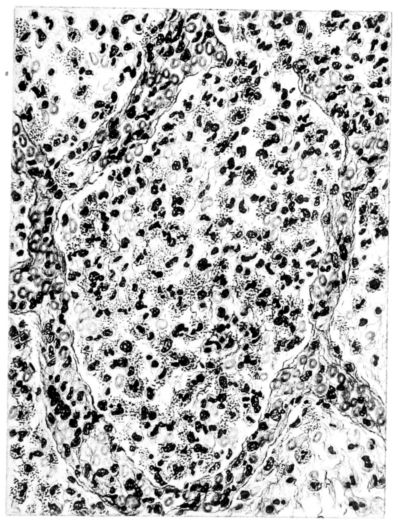

FIG. XXI. AUTOPSY NO. 95. A TYPICAL APLASTIC ALVEOLAR EXUDATE COMPOSED Of RED BLOOD CELLS, FIBRIN, AND BACTERIA. COMPARE FIGURES XX, XXII, AND XXIII.

Sections from those areas of the lung where the involvement is more marked may show a histological picture not unlike that described for the aplastic stage, but, in addition, there are groups of lobules where the exudate is typically purulent and pus cells not only form the greater part of the exudate in the lumen, but are prominent in the distended vessels of the alveolar wall (Fig. XXIX). Often these leucocytes are multilobed and frequently their protoplasm is granulated with phagocytized bacteria. The bacteria are also encountered free in the alveolus along with other elements; namely, red blood cells, strands of fibrin, or precipitated albumin (Fig. XXI). The bacteria, however, are not particularly conspicuous, for generally they are either single, in pairs, or in chains; and it is only when they become clumped to form large masses, often larger than any normal tissue cell, that they attract attention. When this appearance is encountered, the alveolar wall is no longer distinct and well preserved. Although the wall may still be made out, it often stains rather homogeneously and much of the finer architecture is lost in the thrombo-necrotizing process that has been instituted (Fig. XVII).

From this intermediary stage the picture of actual abscess with mortification of bronchiolar and alveolar tissue, as well as of the exudate itself, is readily approached (25, 48, 110, 140) (Fig. XXXI). In the necrotic mass that forms the center of such a focus, the most prominent feature is the bacteria. With hematoxylin they stain intensely as black, 26irregular masses, and their prominence is accentuated by the homogeneous staining qualities (with eosin) of the dead tissue, whether lung or exudate (Fig. XXXII). These abscesses may have central cavities which represent a discharge of their contents and may indicate the position of a bronchiole (Fig. XXXI). The necrosis of the alveolar walls, focal in its distribution as previously described, suggests itself as a forerunner of the more extensive necrosis encountered at this stage.